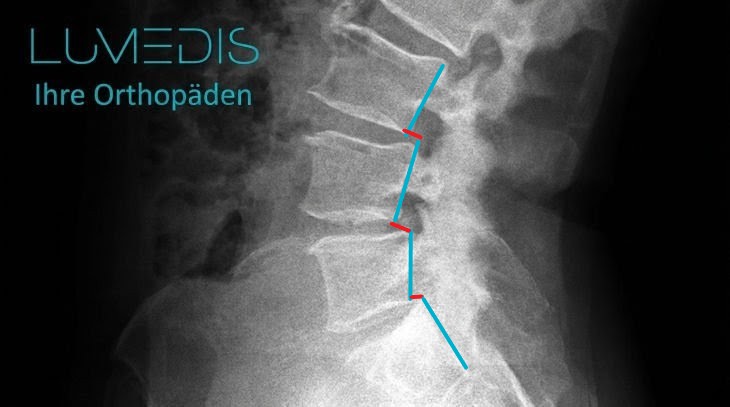

Röntgenbild der LWS mit Wirbelgleiten (Meyerding 1°)

Die türkise Linie zeigt jeweils die Hinterkanten der Wirbelkörper.

Die rote Linie zeigt das jeweilige Wirbelgleiten.